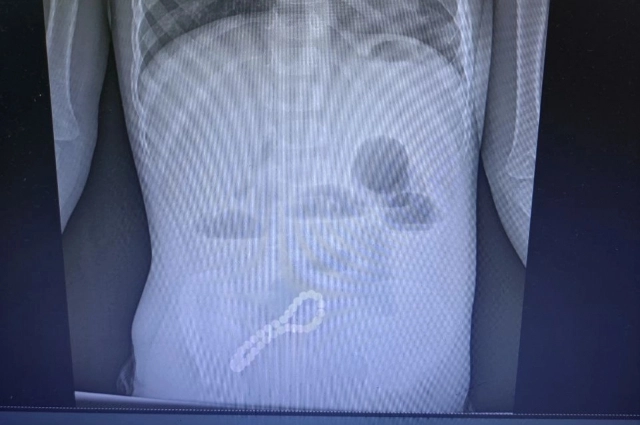

Родители трехлетнего мальчика сначала не заметили пропажу украшения. А вот по своему ребенку стали замечать что-то неладное. Очевидными были проблемы с пищеварением. Сразу обратились к врачу. Малыша госпитализировали в ОДКБ им. Н.В. Дмитриевой. Хирурги заподозрили нарушение функций кишечника. Рентген четко показал: в животе у мальчика есть инородное тело. Причем даже по рентгеновскому снимку родители вполне могли узнать свое украшение...

«Было принято решение об операции. Мы провели минилапаротомию (хирургическое вмешательство, при котором через разрез передней брюшной стенки производится доступ к внутренним органам живота). И увидели, что магнитами, которые притянулись друг к другу, соединены петли кишки, в ее стенке — отверстия. В ходе операции удалили все 30 магнитных бусин: 29 маленьких и одну большую. Сейчас ребенок поправился. Его жизни и здоровью ничего не угрожает», — рассказал заведующий детским хирургическим отделением ОДКБ им. Н.В. Дмитриевой, главный внештатный хирург Минздрава Рязанской области Олег Ларькин.